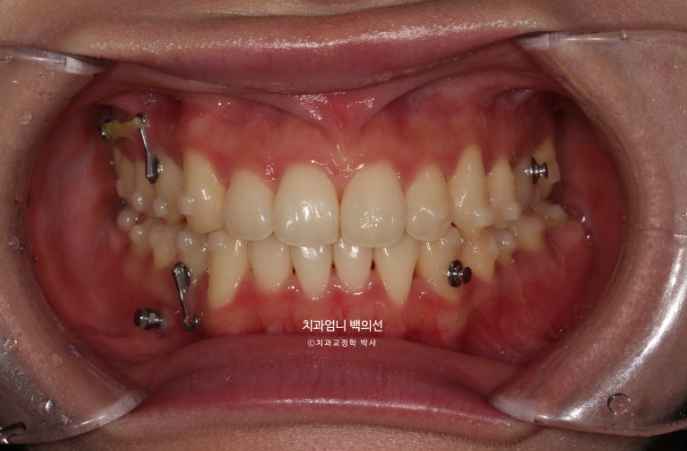

23년 7월 교정치료를 위해 내원한 환자분입니다.

고치고 싶은 것은 중심선 비대칭과 덧니입니다.

왼쪽 위 작은어금니 하나가 선천적으로 없으면 이로 인해 그쪽으로 윗니 중심선이 돌아가 있습니다.

앞니가 뻗쳐 있습니다.

파란 화살표가 원래 작은어금니가 하나 더 있어야할 자리, 즉 선천적으로 결손된 작은어금니 자리입니다.

다행인건 가용한 사랑니 공간이 충분한 점입니다.

입매 돌출감이 미미하여 비발치 치료 권유드렸습니다.

즉 작은어금니 발치 없이 사랑니 공간을 이용하여 교합을 맞추고 중심선을 맞추기로 했습니다.